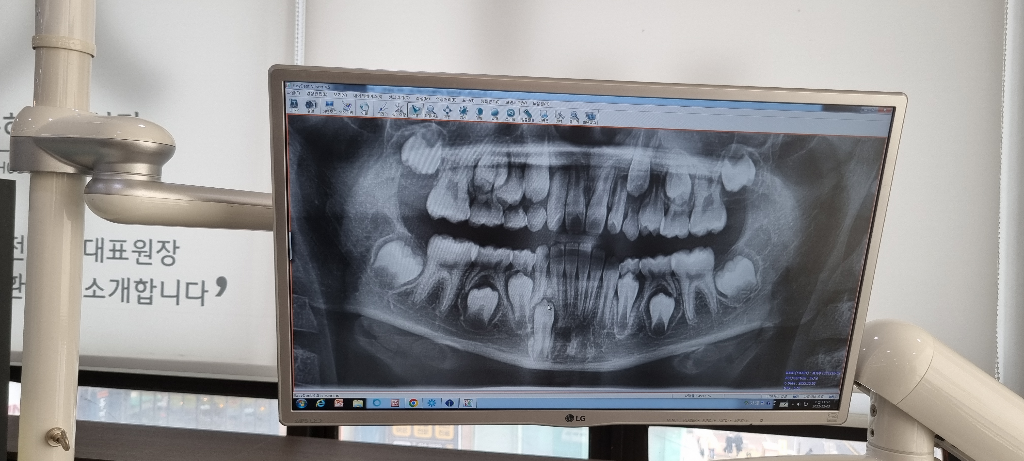

• 2번 째 사진

말씀하신 부위가 뼈이거나 치아로 인하여 맹출이 지연되고 있음이 보입니다. 물론 정확한 것을 판단하기 위해서는 해당 부위에 ct를 촬영해보아야 할 것으로 보입니다. 뼈이거나 치아가 맞다면 대학병원 방문 후 해당 부위의 유치를 조기 발치하고 뼈나 치아를 제거한 다음에 영구치 맹출을 유도해야할 것으로 보여집니다.

과잉치가 잇는거 같네요. 저런경우에는 발치를 해주시는게 좋습니다. 대학병원에가셔서 한번 문의를 해보세요.

과잉치가 있을 수 있습니다. 발치를 하셔야지 영구치가 나올 수 있으므로 수술을 고려하시는 것이 좋겠습니다